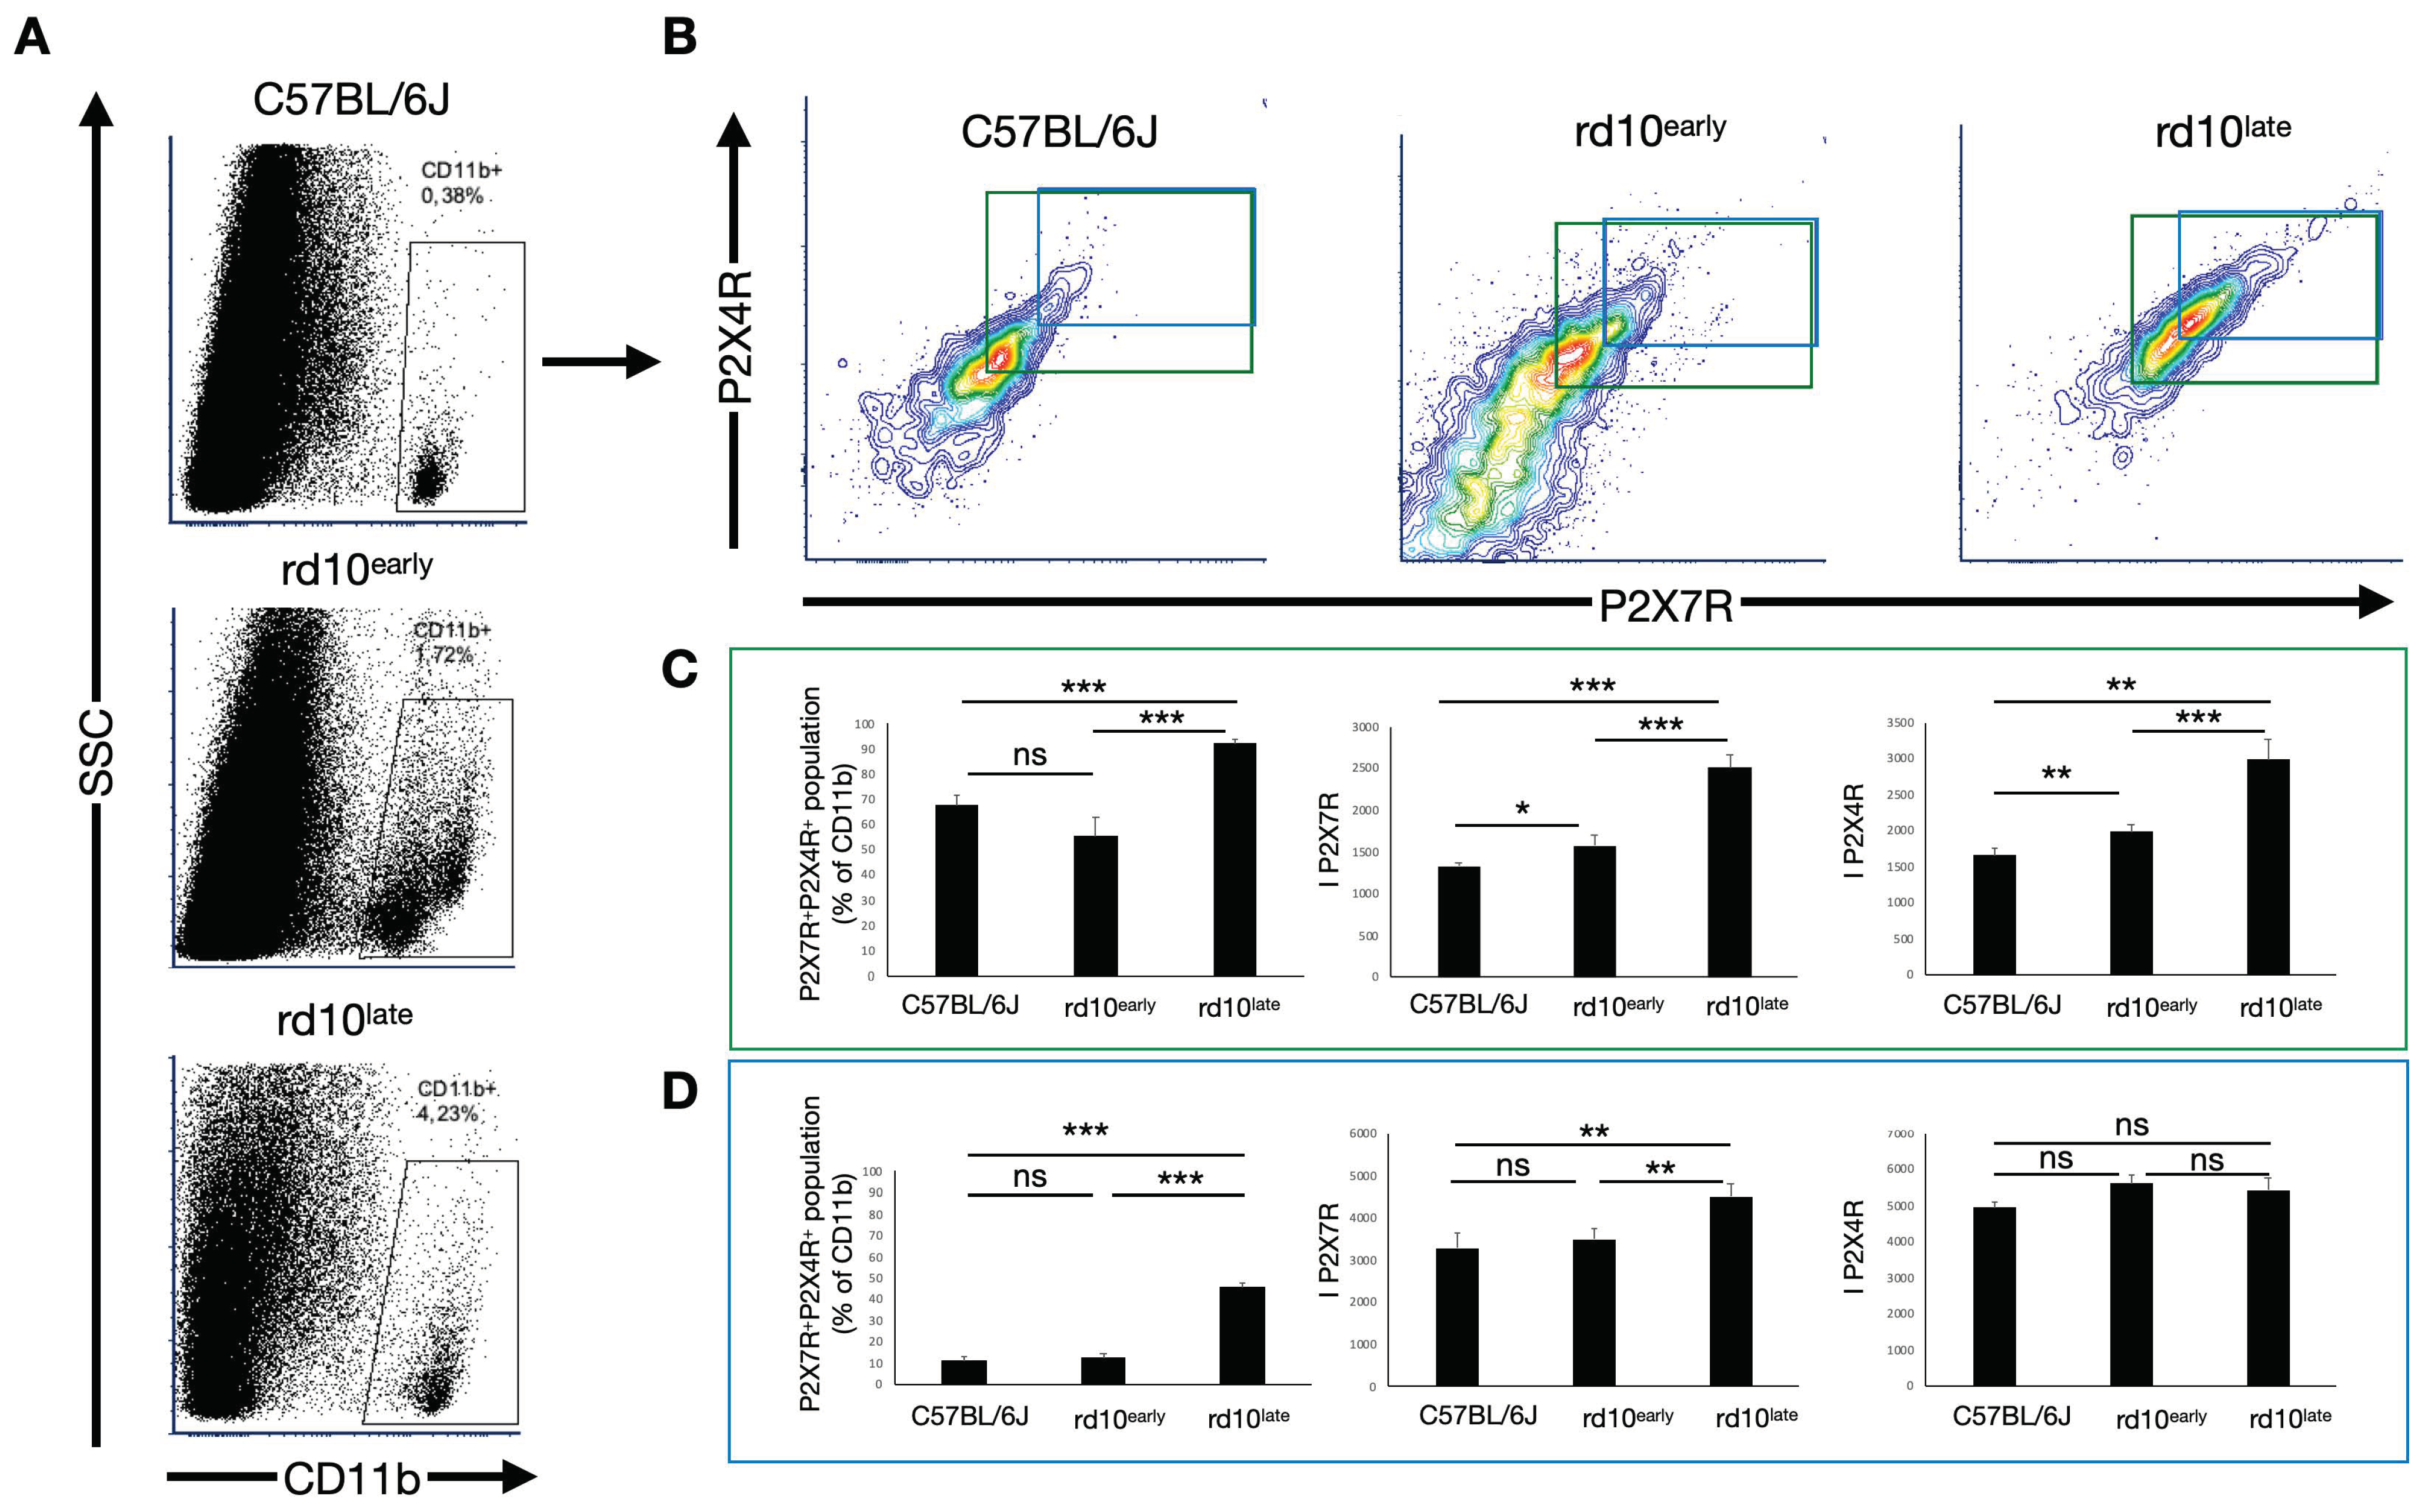

2.4. CD11b-Positive Cells in Degenerating Retinas Overexpress P2X7R but Not P2X4R

2.5. P2X7R and P2X4R Expression Levels Vary in Subsets of CD11b-Positive Cells